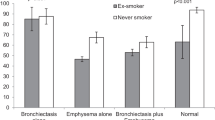

The two most common pulmonary conditions associated with AATD are pulmonary emphysema and bronchiectasis. The pulmonary emphysema tends to be panlobular in distribution and most prominent in the lower lobes but this is not invariable [4]. Upper zone disease and centrilobular distribution can be seen in AATD-related lung disease but this tends to be less common. Similarly, the bronchiectasis noted in those with AATD does not have unique characteristics except for its ubiquity. In one study [5], approximately 94 % of individuals with AATD had computerized tomography (CT) lung radiology consistent with bronchiectasis. In most cases, this bronchiectasis is asymptomatic, the so-called anatomic bronchiectasis.

The single well-powered study enrolled about 180 subjects with approximately half randomized to receive augmentation therapy at standard doses and the other half receiving placebo infusions for 2 years. This study demonstrated a significant preservation of lung tissue comparing the treated to the control group. In addition, an extension study allowed treated subjects to continue on therapy for an additional 2 years and rolled the placebo subjects onto treatment for this second 2-year period. The extension study demonstrated that, during the second 2 years of therapy, the rate of loss of lung tissue slowed even further in the group on 4 years of augmentation therapy. See Fig. 6.2. In addition, those initially receiving placebo showed a decrease in the rate of loss of lung tissue once they were started on augmentation therapy for the 2 years of the extension study. An interesting finding in this study was that the trough blood levels of AAT were inversely correlated with the rate of lung tissue loss. See Fig. 6.3.

Effect of augmentation therapy (A1PI) versus placebo on rate of lung density decrease during the double-blind and open-label portions of the trial in all patients. Values on graph are annual rates of decrease calculated from CT densitometry at total lung capacity. A1PI n = 92; placebo n = 85 during double-blind period. A1PI n = 50; placebo n = 47 during open-label period. p = 0.03 during the double-blind portion (reprinted with permission from Ref. [32])